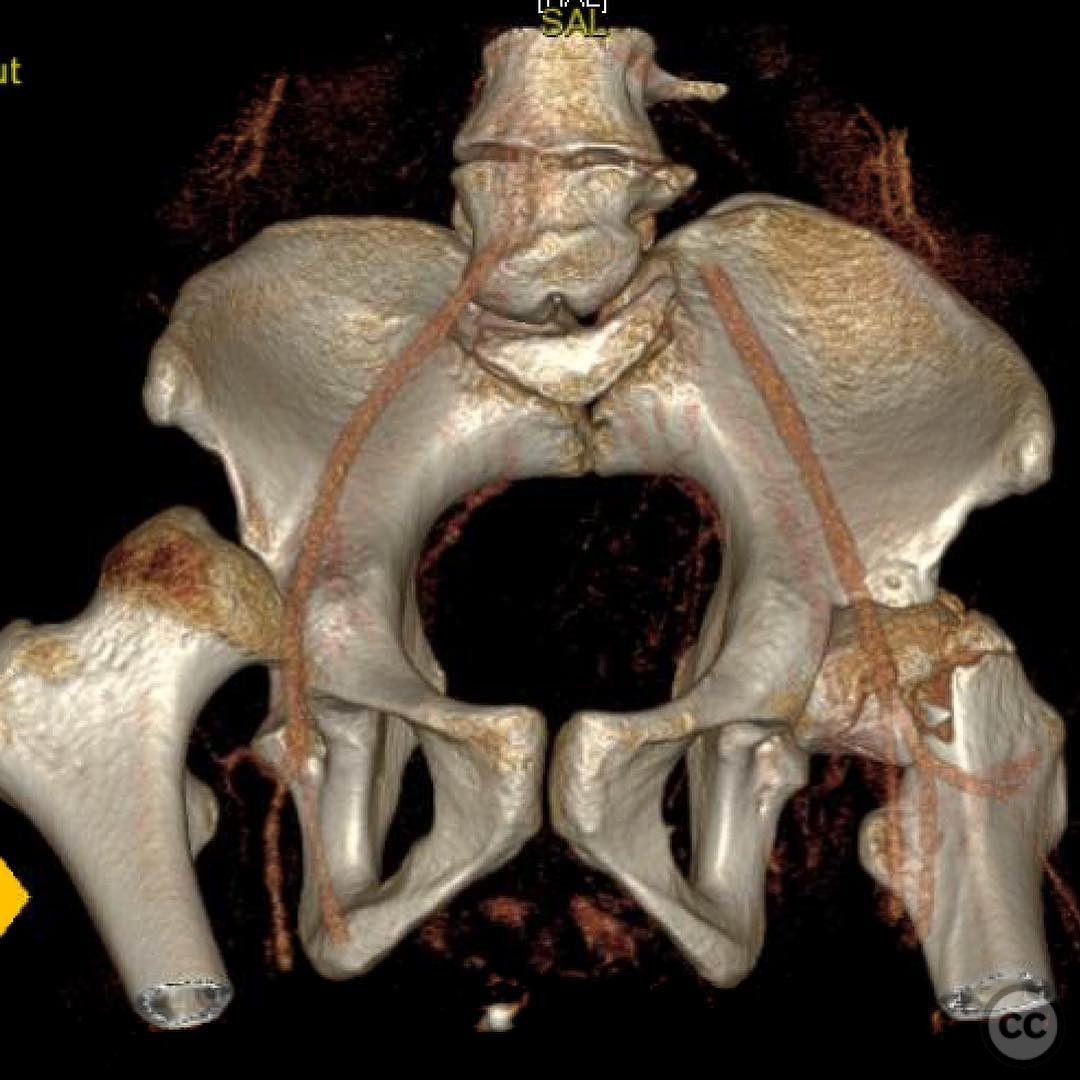

Pipkin IV Femoral Head Fracture with Ace...

Seattle, United States

Femur - AO/OTA 3x

Pipkin IV Femoral Head Fracture Dislocat...

Pipkin IV Femoral Head Fracture with Fem...

Pipkin 2 + cranial peripheral acetabular...